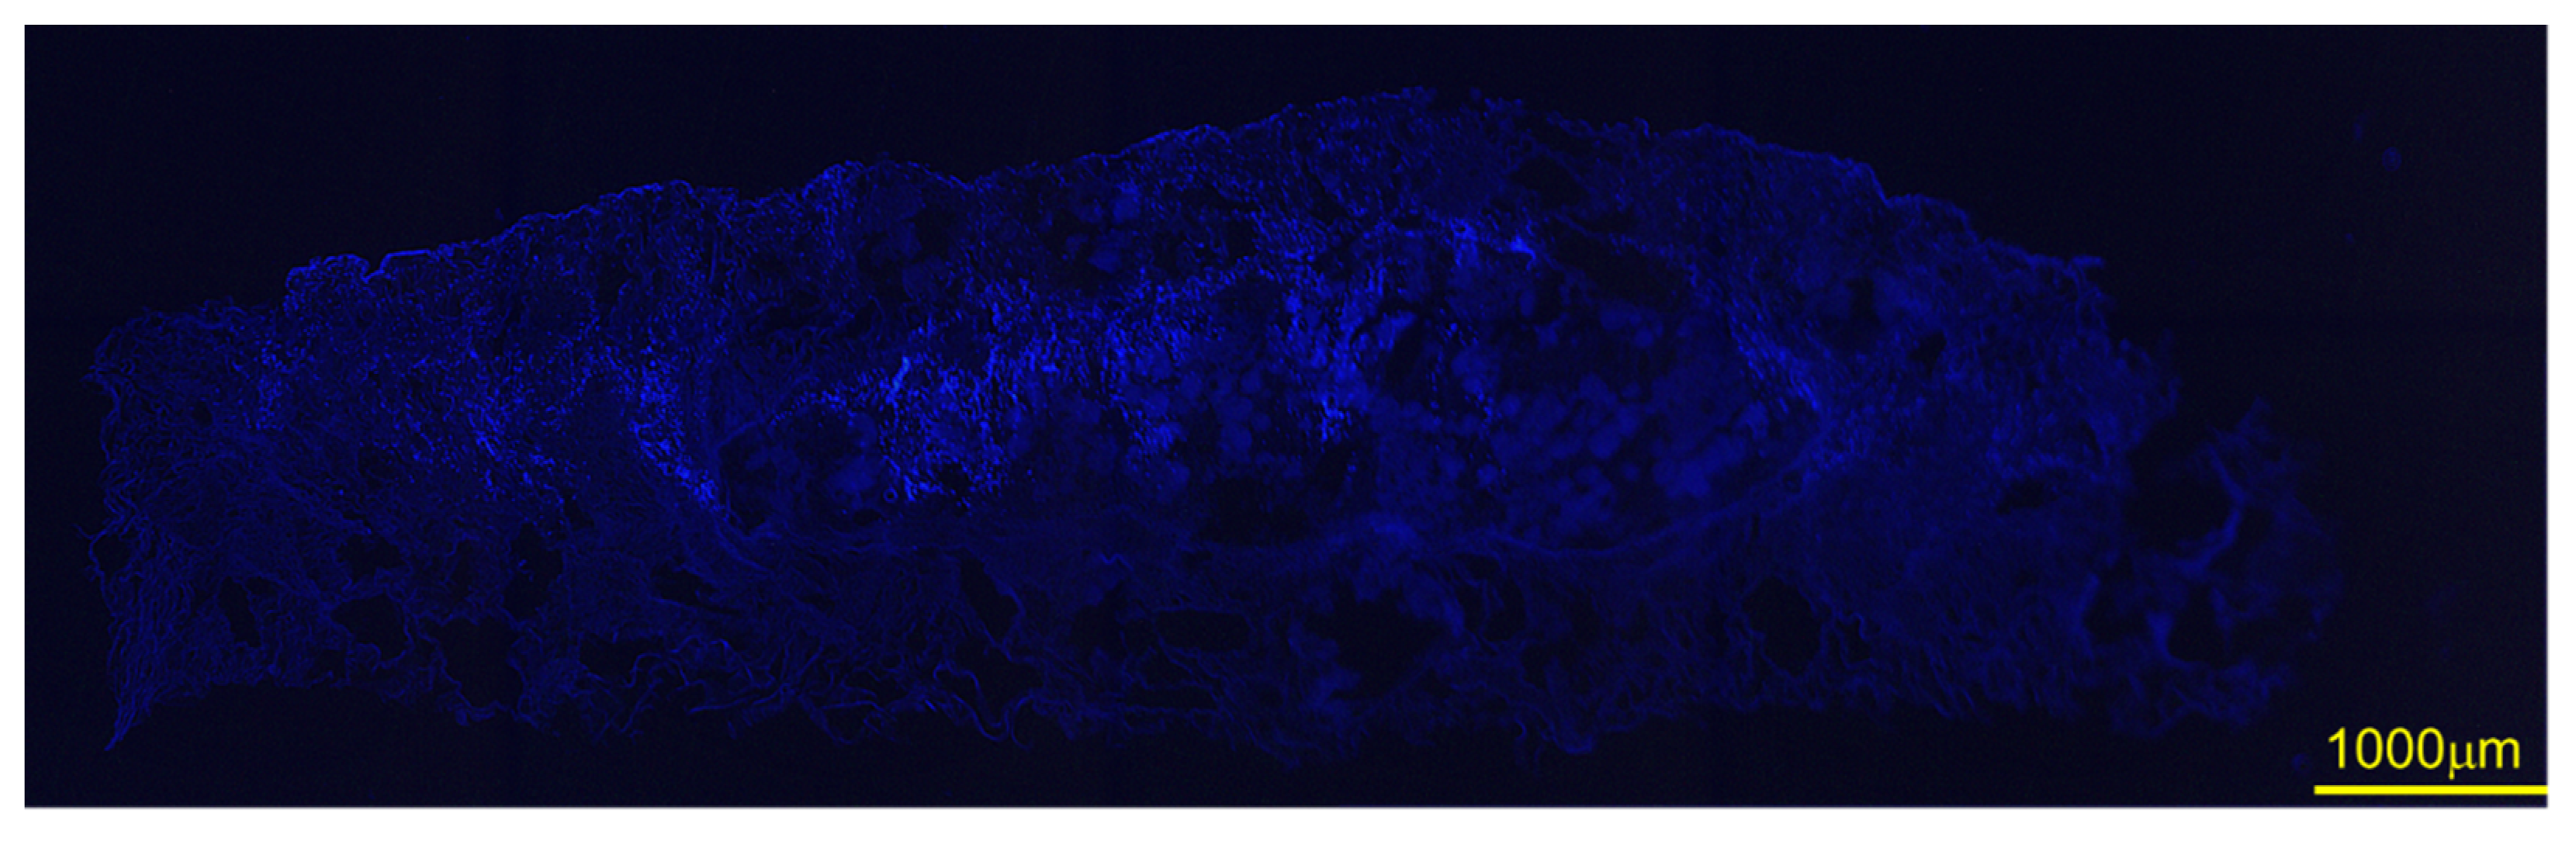

Figure 10 depicts the cell attachment behavior of DFATs on α-TCP/GS. Several cells attached to α-TCP; some cells displayed a spreading morphology, a characteristic form of DFAT. Figure 11 is an image of DFAT seeded on α-TCP/GS and DAPI stained; the cell nuclei of DFAT are stained in the center of α-TCP/GS.

Figure 11.

Images of DFAT seeded on α-TCP/GS and stained with DAPI. Scale bar is in 1000 μm.